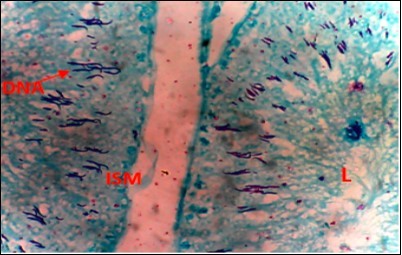

Figure 3.Normal Control (NC) X400 – Section of testis showing numerous deeply stained DNA with magenta color.

Figure 4.Diabetic Control (DC) X400 – Section of testis showing scanty DNA stained with magenta colour. DNA strands are cross linked and appear in clusters

From findings in this study, irregular and distorted arrangements of DNA in all diabetic groups (Groups B, C, D, E and F) when compared with the normal control group, may have been due to displacement of sertoli cell within the germinal epithelium of seminiferous tubules. Strands of DNA were also seen arrange in clusters in diabetic groups, showing altered and defective structure which might have resulted from base free side deletion, frame shift, cross-linking and chromosomal rearrangement. The intensity of magenta colour development in Feulgen reaction for DNA demonstration was proportional to DNA concentration. There was reduced colour intensity in all diabetic groups (Groups B, C, D, E and F) when compared with the normal control. This is in line with report from Aitken and Krausz (2001). However the degree of distortion and cross-linking of DNA strand in the group of diabetic animal models placed on high dose (1000mg/kg.bw) of A. polytricha which may be a sign of amelioration. Groups C, D and F placed on 250mg/kg.bw A. polytricha, 500mg/kg.bw A. polytricha and standard anti-diabetic drug (metformin) respectively did not show remarkable differences in terms of DNA arrangements when compared with the diabetic control group. Groups D (500mg/kg.bw A. polytricha) and group E (1000mg/kg.bw) showed visible improvement in magenta colour intensity when compared with the diabetic control group.